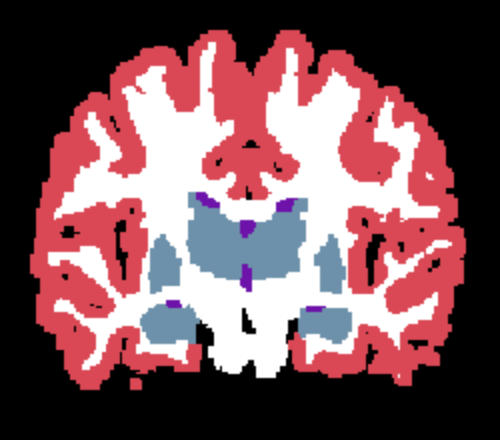

Results. Qualitative segmentation results are presented in Figure 3 and quantitative results are summarized in Table 5. Figure 3 shows that Learn2Synth produces cleaned and more accurate segmentation results compared to SAMSEG and naive SynthSeg, which is further validated by the higher Dice scores reported in Table 5. Learn2Synth also obtains higher Dice scores than the two SynthSeg variants that incorporate real data. These results highlight the effectiveness of Learn2Synth in enhancing segmentation quality for complex real-world data.

Results. Quantitative results are summarized in Table 6, and graphically represented in Figure 4. The supervised UNet achieves the highest Dice score on Buckner39, particularly when trained with 29 training samples, reaching , which is not surprising. However, its performance drops significantly on FLASH scans, highlighting its limited generalization ability. Learn2Synth, on the other hand, demonstrates improved generalization across datasets, achieving Dice scores of approximately 0.79 across all FLASH sequences when trained with as few as 5 training samples. Surprisingly, Learn2Synth improves its Dice over the SynthSeg baseline on MPRAGE scans (as expected) but also on all FLASH scans. These results suggest that Learn2Synth effectively generalizes to unseen imaging conditions.